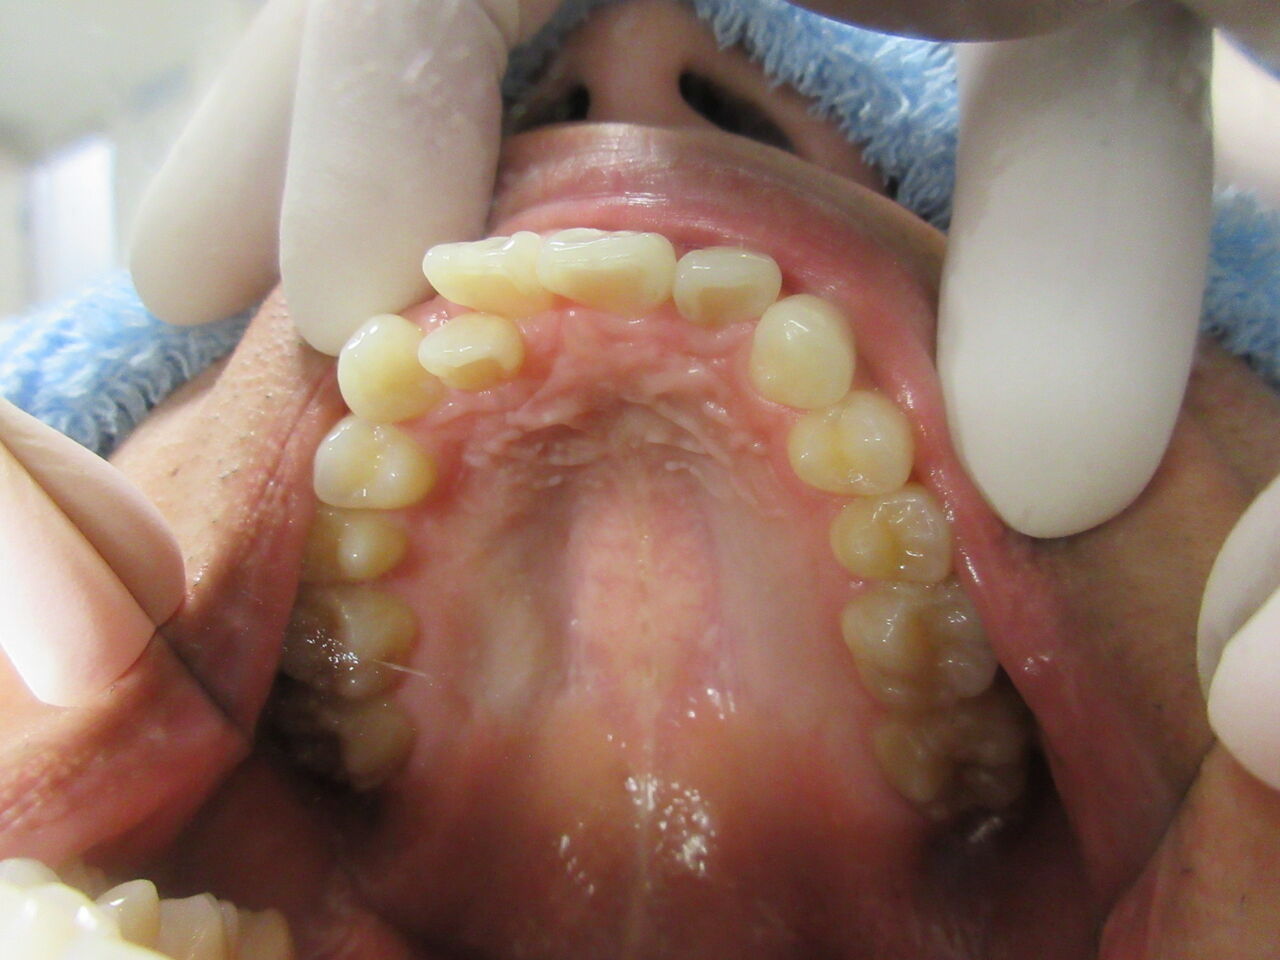

乳歯